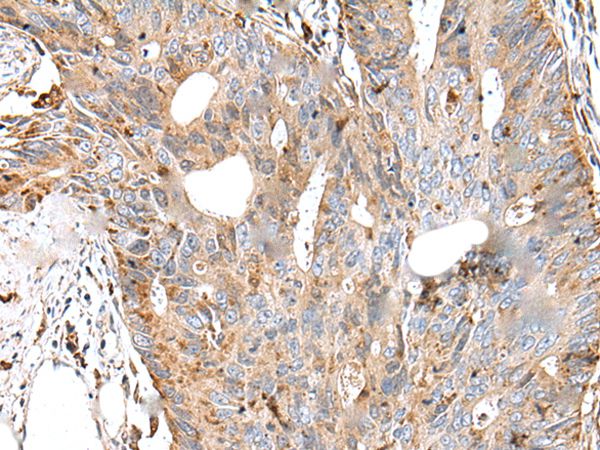

The image on the left is immunohistochemistry of paraffin-embedded Human colorectal cancer tissue using CTSS Antibody at dilution 1/30, on the right is treated with synthetic peptide. (Original magnification: x200)